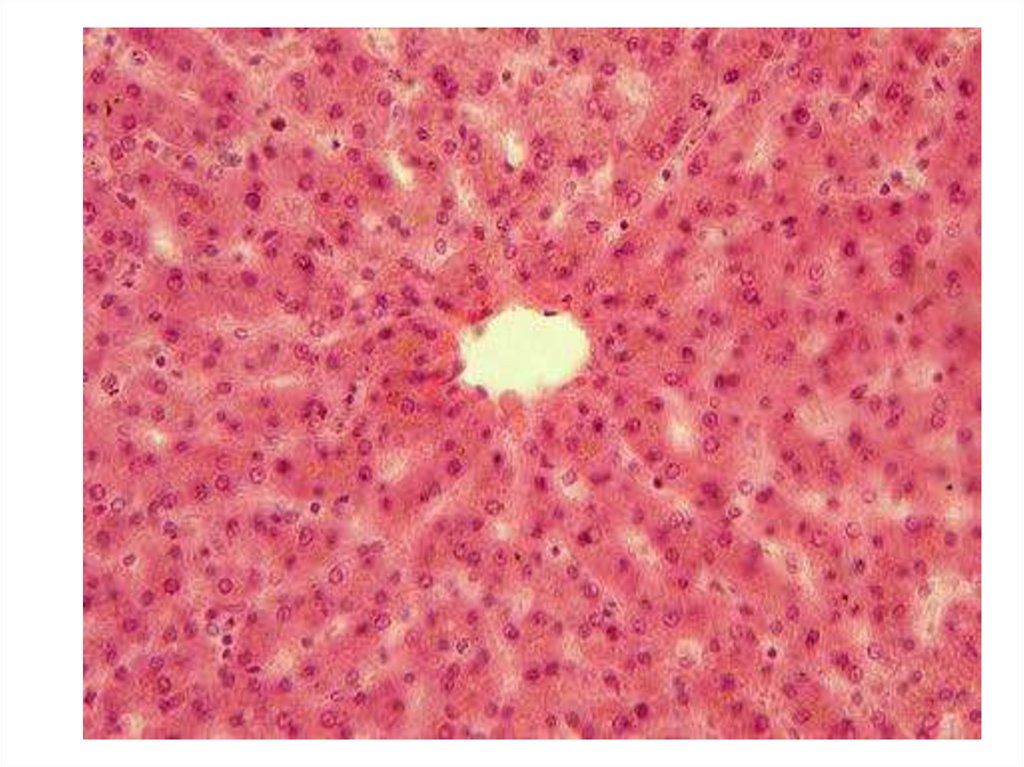

biology

Срезы тканей